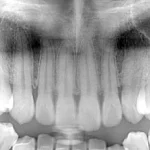

3 Key Differences Between Extraoral Dental Bitewings and Intraoral Dental Bitewings

The Seven Most Common Questions When Implementing a New Dental Intraoral Sensor System